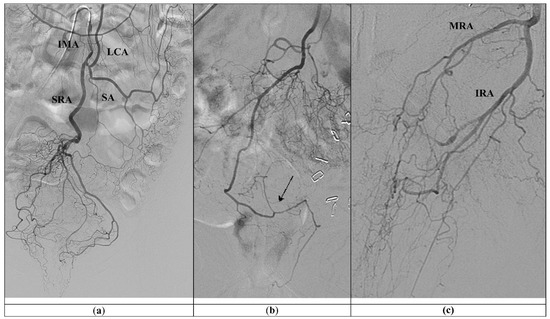

The Emborrhoid is an innovative non-surgical technique for the treatment of severe hemorrhoidal bleeding. Patient selection and the impact on quality of life have not been fully investigated. This prospective observational study aims to evaluate the clinical outcomes after Emborrhoid in patients with high surgical risk. All patients with high surgical risk and anemia due to hemorrhoids were enrolled. Clinical data and previous blood transfusions were collected. The Hemorrhoidal Disease Symptom Score and Short Health Scala were completed before the procedure and during the follow-up visits at 1, 6 and 12 months. Transfusions and serum hemoglobin level variations were registered. Perioperative complications and the recurrence of bleeding were assessed. Trans-radial/femoral embolization of superior rectal artery, and/or middle rectal artery was performed with Interlock and Detachable Embolization Coils. From September 2020 to February 2022, 21 patients underwent a superselective embolization of all branches of the superior rectal artery. The transradial approach was most frequently performed compared to transfemoral access. After the procedure, no signs of ischemia were identified; three minor complications were observed. The mean follow-up was 18.5 ± 6.0 months. At the last follow-up, the mean increase of hemoglobin for patients was 1.2 ± 1.6 g/dL. Three patients needed transfusions during follow-up for recurrent hemorrhoidal bleeding. The Hemorrhoidal Disease Symptom Score and Short Health Scala decreased from 11.1 ± 4.2 to 4.7 ± 4.6 (p < 0.0001) and from 18.8 ± 4.8 to 10.2 ± 4.9 (p < 0.0001), respectively. Patients who had given up on their daily activities due to anemia have returned to their previous lifestyle. Emborrhoid seems to be a safe and effective option for the treatment of bleeding hemorrhoids in frail patients. The low complication rate and the significant reduction of post-defecation bleeding episodes are related to the improvement of the hemorrhoidal symptoms and patients’ quality of life. Full article

Purpose: The purpose of this study was to prospectively evaluate the efficacy and safety of a new, bare platinum, detachable microcoil as a metallic embolization agent in the treatment of hemorrhoidal disease. Material and Methods: This prospective single-center study evaluated a new, bare [...] Read more.

Purpose: The purpose of this study was to prospectively evaluate the efficacy and safety of a new, bare platinum, detachable microcoil as a metallic embolization agent in the treatment of hemorrhoidal disease. Material and Methods: This prospective single-center study evaluated a new, bare platinum, electrical, detachable microcoil (Prestige plus coil (Balt Montmorency France)) for use in vascular embolization in patients with hemorrhoidal disease. Between January 2020 and January 2021, 24 embolization procedures were performed in 21 patients (12 males, 9 females; mean age 44.3 ± 7.3). The inclusion criteria were: (a) participants with grade I, II and III hemorrhoidal disease on the Goligher classification; (b) patients older than 18 years of age with a score of greater than 4 on the French bleeding score (FBS) scale; (c) patients with scores greater than 2 on the scale of discomfort proposed by Tradi and Farfallah. (d) patients who underwent treatment that included the use of the new novel coil (Prestige plus coil (Balt)) as an embolic material. The exclusion criteria were participants who failed to provide informed consent and participants diagnosed with rectal bleeding due to other causes (cancer, fissures or others). Participants with severe renal insufficiency, non-correctable coagulation abnormalities and adverse reactions to the contrast medium not correctable with medication were also excluded. The symptoms, technical aspects, the transarterial approach, clinical and technical success complications and short-term outcomes were assessed. Results: Technical success was obtained in 100% of the cases. Seventeen (80.9%) patients experienced improvements in their hemorrhoidal disease. The VAS and QL scores improved by 4 and 1.5 points (81.2% and 87.5%), respectively, after embolization (pV: 0001). Three (14.2%) patients underwent a second embolization due to rebleeding. One patient (4.7%) underwent surgery. No major complications were observed. Three patients had minor complications. The assessment of subjective post-treatment symptoms and QL surveys showed significant differences from the baseline survey. Likewise, the measurement of the degree of satisfaction using a telephone survey at 12 months revealed a high degree of patient satisfaction over 10 points (mean 8.3 ± 1.1). Conclusions: The present study demonstrates that the use of the new, platinum, detachable, electrical microcoil is safe and well-tolerated in the treatment of hemorrhoidal disease. Key points: Catheter-directed hemorrhoidal dearterialization (CDHD) is the procedure of embolization with embolic agents for the treatment of internal hemorrhoids. CDHD is a simple and safe procedure that is accepted by patients and preserves the anal sphincter; it presents few complications when metal devices or microspheres are used as embolic agents. As the recommended embolization agent in treatments, the Prestige electrical, detachable coil is a safe, easy-to-use and effective arterial embolic device. Full article